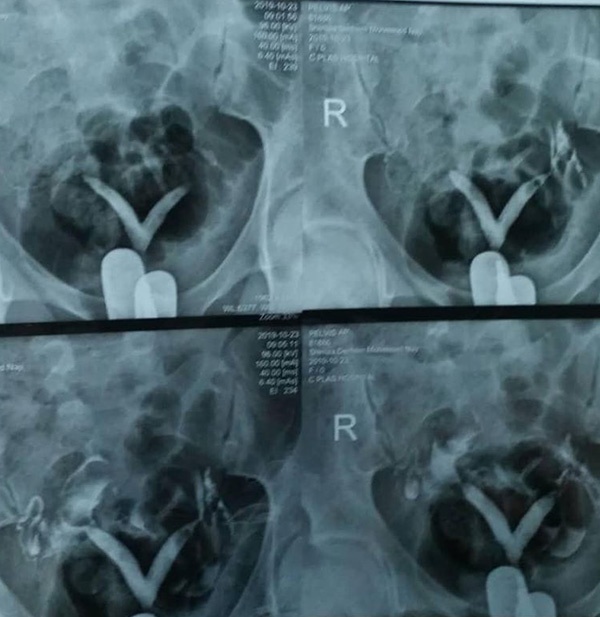

البروفيسور: اتت المريضة تعاني من اسقاطات سابقة الرابعة اخرها وبعد الاطلاع على الاشعة و الفحوصات .. وجدنا أن الفتاة لديها رحمين اثنين .. سبحان الله .

وهذا سبب رئيسي في حدوث الاسقاطات المبكرة والمتكررة ...

تقرر إجراء عملية دمج الرحمين في رحم واحد .. للحد من الاسقاطات .